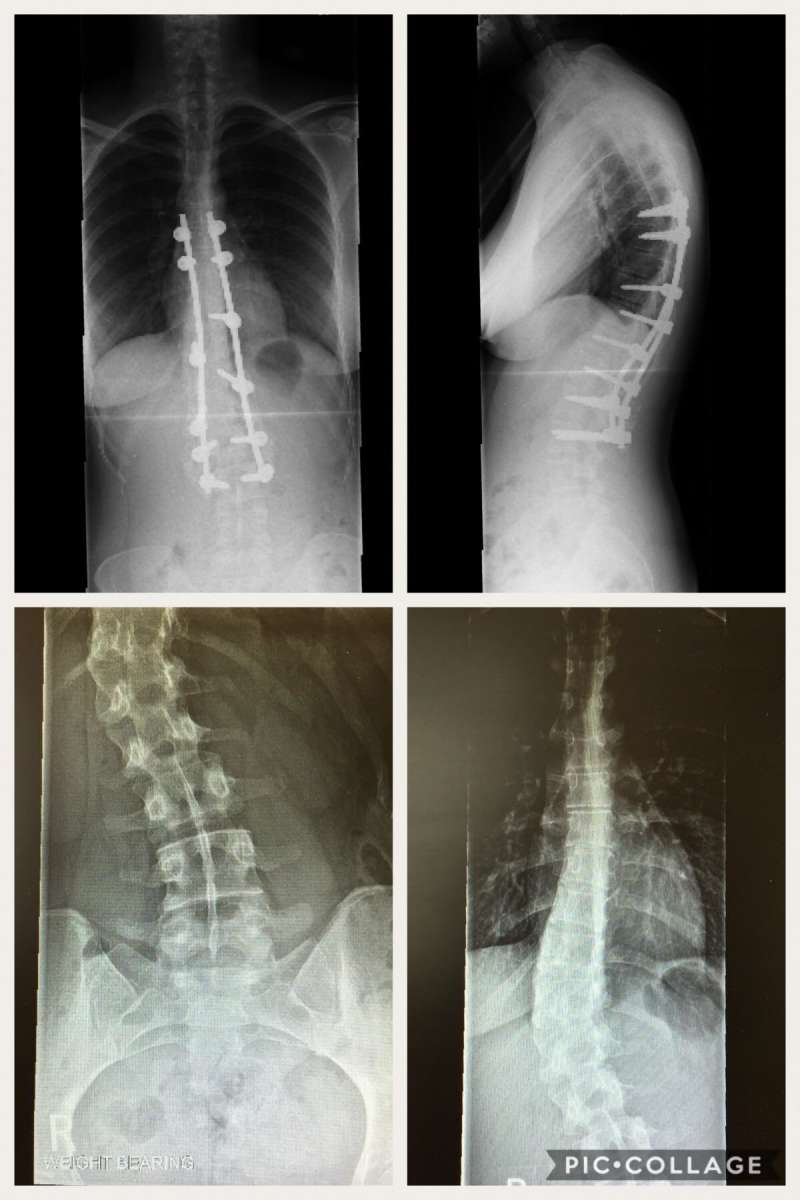

▼由於脊椎側彎矯正手術是在脊椎骨上鎖上鋼釘、鋼鈎,把上下的骨頭用外力拉直、轉正,聽起來真的令人心驚膽戰。如果側彎真的非常嚴重的話,還必須從身體正面對韌帶、椎間盤、軟骨打上拉力支架!女網友也貼出她手術前的X光照片,告誡大家如果脊椎側彎不是天生的話,一定是日常生活所「累積」出來的,尤其長時間坐著又翹腳的話,很容易會讓骨頭歪掉!